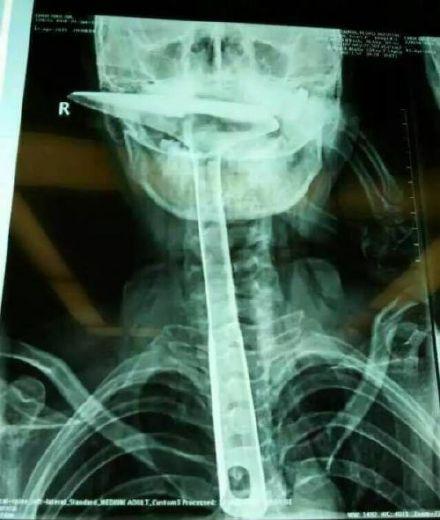

陈女士被紧急送到东莞第五人民医院,医生拍片显示,整个铁锅铲把手已经在胸里了,病情严重。当晚,陈女士就被转到了康华医院。“患者来院时,嘴巴里只剩一个锅铲铲勺露在外面,整个锅铲手柄已经被插入到食道里了。”康华医院胸外科接诊医生陈羽彪说,检查发现,锅铲总长大概30公分长,手柄直径约2.5公分,整个已经插入食道,食道表皮粘膜损伤严重,且被捅破了一个洞,“而且,手柄已严重挤压到了肺部,导致右肺部已无法正常扩张。”

“这样的病例,不说100年难遇,也是50年难遇了。”康华医院胸外科主任肖朴说,患者情况严重,医院立即组织专家会诊。“胸腔全是大血管,一旦拔出就有可能大出血,危及性命。”当天晚上11点,医生决定为患者进行一期手术即食道扩置手术,“我们先将锅铲从食道里面拔出来,由于胸位食道受损严重,只能切除了。”

医生介绍,食道总长约25公分,患者切除了20公分,切除部分主要集中在胸位段,食道只保留到了颈部,只能露出来进行医学处理,吞咽口水、积液进行人工及时清理更换。”